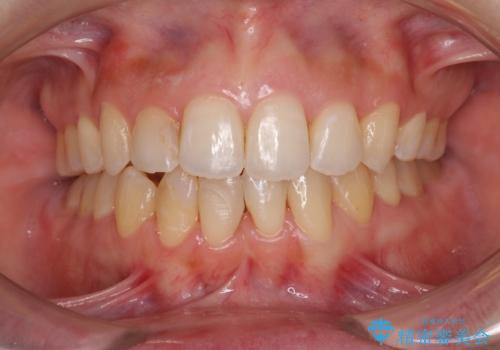

インビザライン・モデレートを用いて気になる後戻りを矯正治療

担当医 藤巻太一朗

前歯のガタつきを改善 抜歯矯正後の後戻り

担当医 草深敏毅